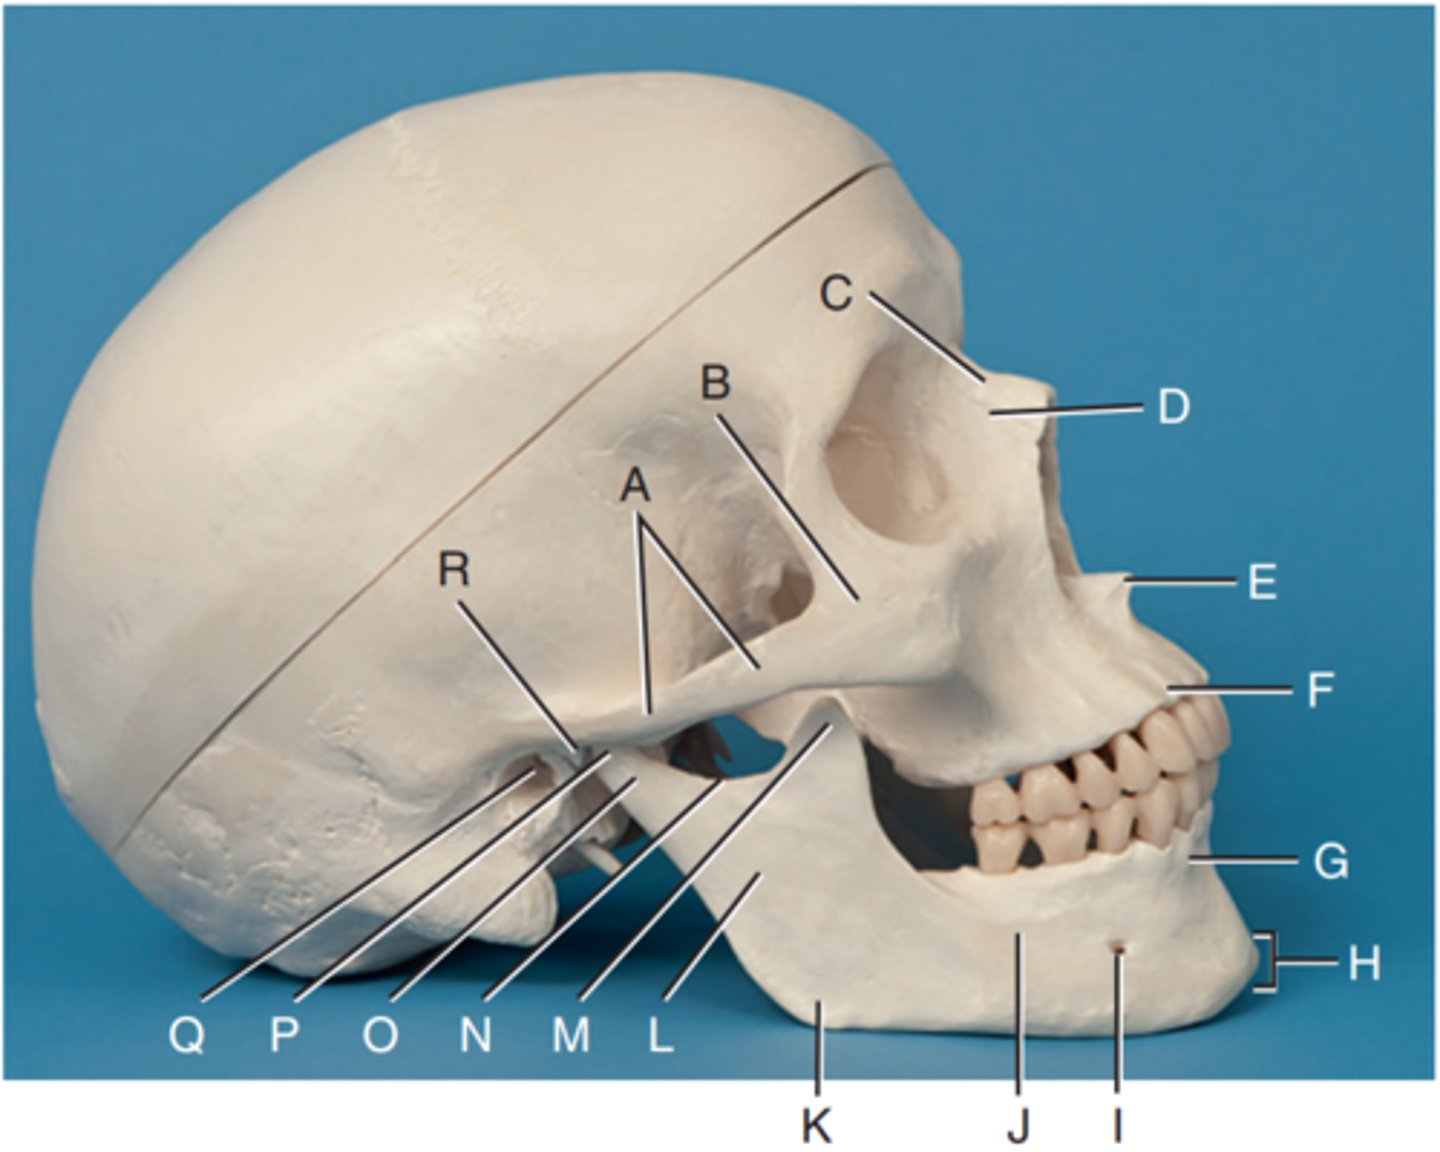

Zygomatic arch

Label A

Right zygomatic bone

Label B

Right nasal bone

Label C

Frontal process of right maxilla

Label D

Anterior nasal spine

Label E

Alveolar process of maxilla

Label F

Alveolar process of mandible

Label G

Mentum or mental protuberance

Label H

Mental foramen

Label I

Body of mandible

Label J

Angle (gonion)

Label K

Ramus of mandible

Label L

Coronoid process

Label M

Mandibular notch

Label N

Neck of mandibular condyle

Label o

Condyle or head of mandible

Label P

EAM

Label Q

TM fossa of temporal bone

Label R